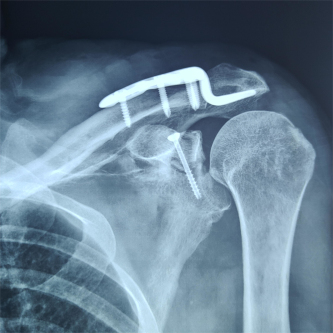

(术后影像)

近日,创伤外科中心A区张立峰教授团队成功完成91直播 首例也是自治区首例“天玑”II骨科手术机器人导航下精确定位经皮内固定肩关节盂骨折,在机器人的帮助下做到了最佳置钉角度和最佳置钉位置,本次手术减小了患者手术切口,且缩短了手术时间,同时缩短了骨科医生在X线下辐射时间。本例手术的成功实施,标志91直播 创伤外科骨科机器人导航下微创手术治疗达到国内先进水平。

“天玑”Ⅱ骨科手术机器人用于辅助医生精确定位植入物或手术器械,可广泛应用于骨科手术,其临床精度可达1mm以内。自2021年91直播 成功引进后,已完成各类骨科手术。本次应用骨科机器人进行肩关节盂骨折手术治疗,进一步拓展了“天玑”II骨科机器人的诊疗范围,完美呈现了“人机结合”,更为创伤急救中心的创新治疗带来新思路。创伤外科中心将继续充分利用骨科机器人的技术优势在新的领域开展临床治疗,提高自治区创伤救治水平,更好地造福患者。